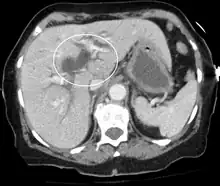

| Jaundice caused by pancreatic cancer | |

Post-hepatic jaundice (obstructive jaundice), is caused by a blockage of bile ducts which transport bile containing conjugated bilirubin out of the liver for excretion. The following is a list of conditions that can cause post-hepatic jaundice:

- Pancreatic cancer of the pancreatic head